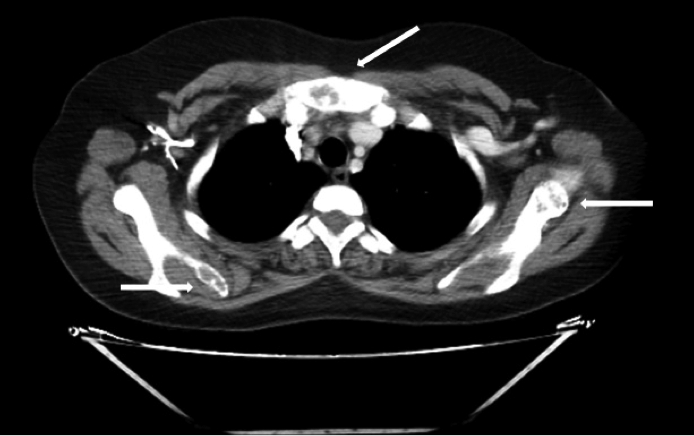

Ante la sospecha clínica de tumores pardos múltiples versus enfermedad metastásica se realiza IC con Oncología y en conjunto se solicitaron los siguientes estudios, que informaron como positivo: a) TAC de tórax, abdomen y pelvis (con contraste): leve enfisema centrolobulillar bilateral, opacidades nodulares con densidad de partes blandas (LSD y LSI). Resto de los órganos normales, no adenomegalias. Presencia de múltiples lesiones osteolíticas a nivel de todos los cuerpos vertebrales, esternón, región anterior de varias costillas, húmero, sacro, y porción visible de ambos ilíacos (Figuras 2, 3 . 4 A); b) TAC de cuello (con contraste): múltiples lesiones osteolíticas en la columna cervical.